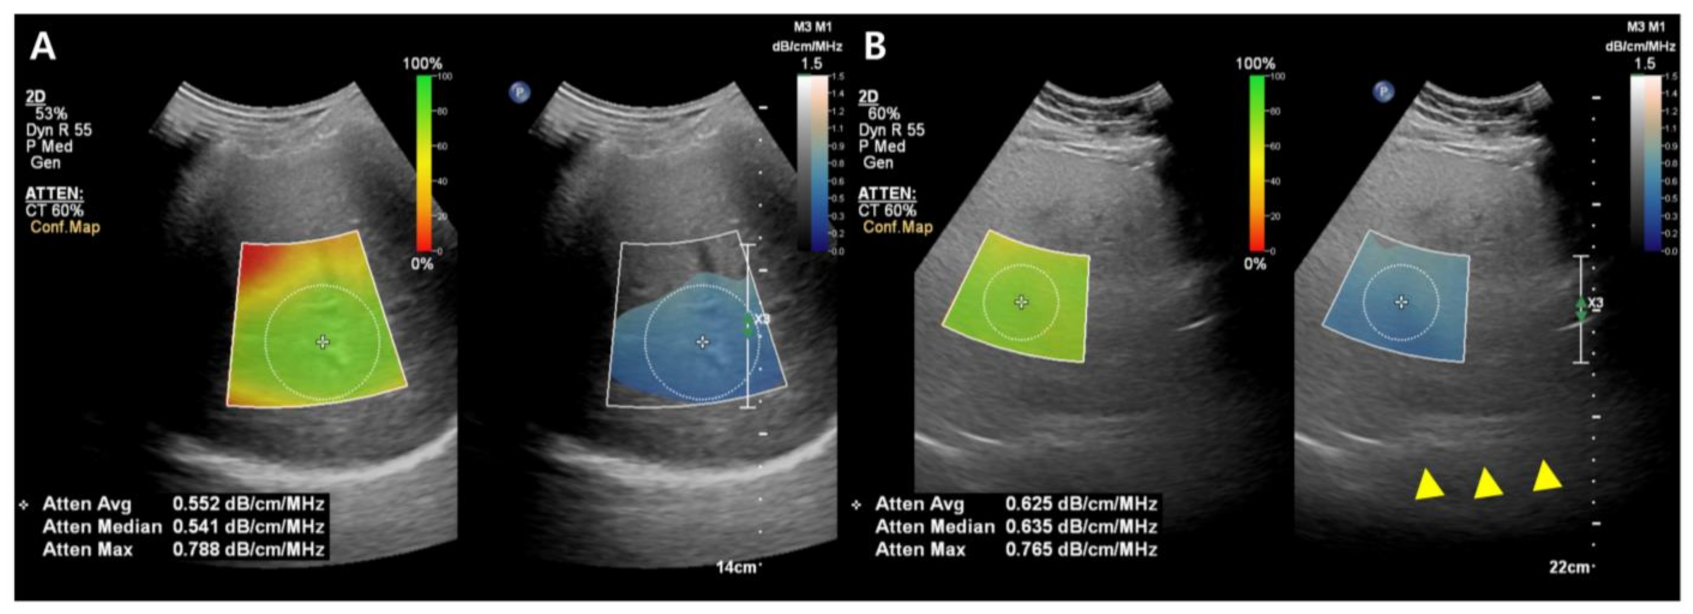

2.3.2. B-Mode Ultrasound-Guided Attenuation Imaging